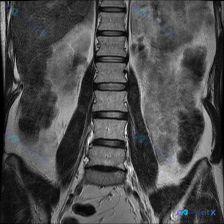

整理到一份腰椎MRI T2冠状位的影像资料,大家先看一眼: 核心影像表现: - 腰椎明显向左侧弯曲,呈“C”型,顶点在腰椎中部 - 椎体形态基本完整,未见明确骨质破坏或压缩 - 椎间盘T2信号普遍减低(偏暗),提示脱水退变 - 侧弯节段椎间隙左右不对称:右侧张开,左侧闭合 - 两侧旁椎肌肉(腰大肌、...

整理了一份腰椎MRI的读片讨论资料,先看冠状位T2加权像的客观表现: 1. 脊柱排列:腰椎向左侧凸(Levoscoliosis),椎体有旋转,中轴线不平直 2. 椎间盘:多节段下腰椎T2信号明显减低(“黑盘”征),提示脱水退变;凹侧(左侧)椎间隙更窄,有挤压 3. 椎体/软组织:椎体边缘有骨赘;骨髓...

整理了一份腰椎MRI T2序列冠状位的影像资料,核心影像表现如下: 1. 脊柱排列:明显的脊柱侧弯(C型,向右侧弯曲),椎体边缘欠光滑,部分可见低信号骨质增生影 2. 椎间隙:多个椎间隙高度不对称,凹侧(右侧)明显变窄 3. 椎间盘:多个腰椎间盘T2低信号,提示脱水、变性 4. 小关节:侧方小关节突...